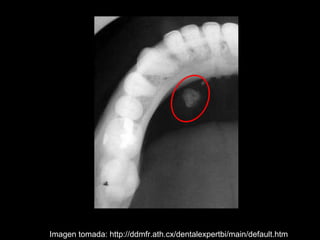

La sialolitiasis es la formación de obstrucciones mineralizadas en las glándulas salivales, causadas por el depósito de calcio y fósforo. Puede presentarse en las glándulas salivales mayores y menores, causando inflamación e hinchazón e incluso dolor durante las comidas. Los sialolitos se ven en radiografías como densidades radiopacas de varias formas y tamaños dentro de los conductos glandulares. El diagnóstico diferencial incluye otras imágenes radiopacas en los tejidos blandos.